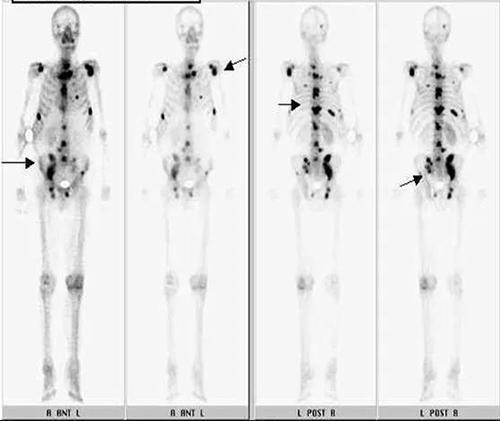

骨扫描出癌的表述语,肺癌骨转移骨扫描图片

肺癌骨转移骨扫描图片

骨扫描骨转移

骨扫描显示骨转移图片

骨扫描图片

全身骨扫描图片

骨扫描图片怎么看